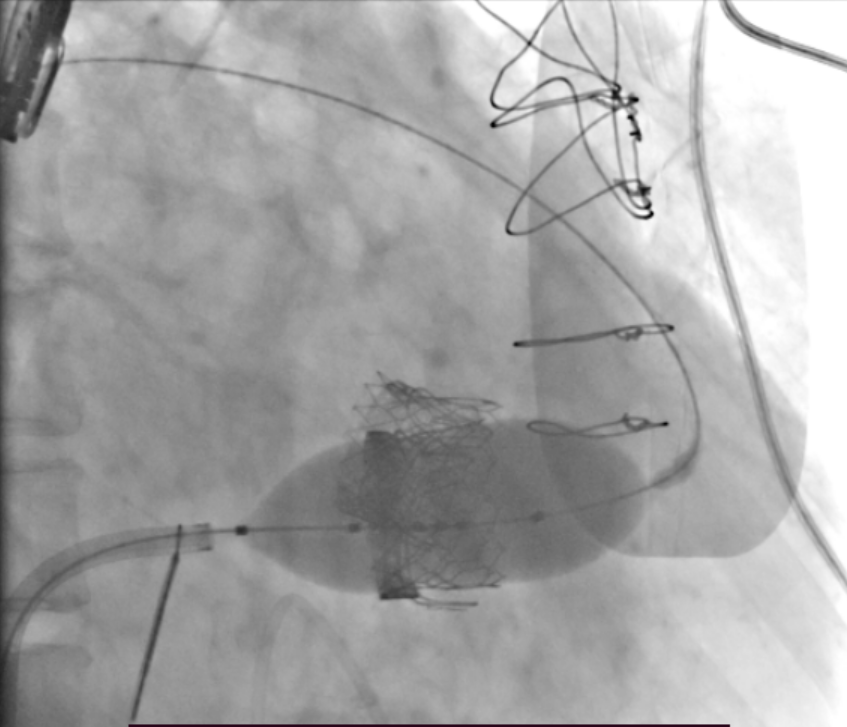

患者全麻后,穿刺右股静脉建立通路,穿刺房间隔,选用18mm球囊对房间隔进行扩张。泥鳅导丝跨二尖瓣后,根据术前评估情况,在180次/分快速心室起搏下,收缩压降至50mmHg,选用26mm Prizvalve®球扩瓣进行植入。瓣膜定位精准,释放顺利,撤出输送系统。随后,在圈套器的辅助下,导丝跨过三尖瓣,根据术前评估情况,选用29mm Prizvalve®球扩瓣进行植入。手术顺利完成。

二尖瓣球扩瓣释放